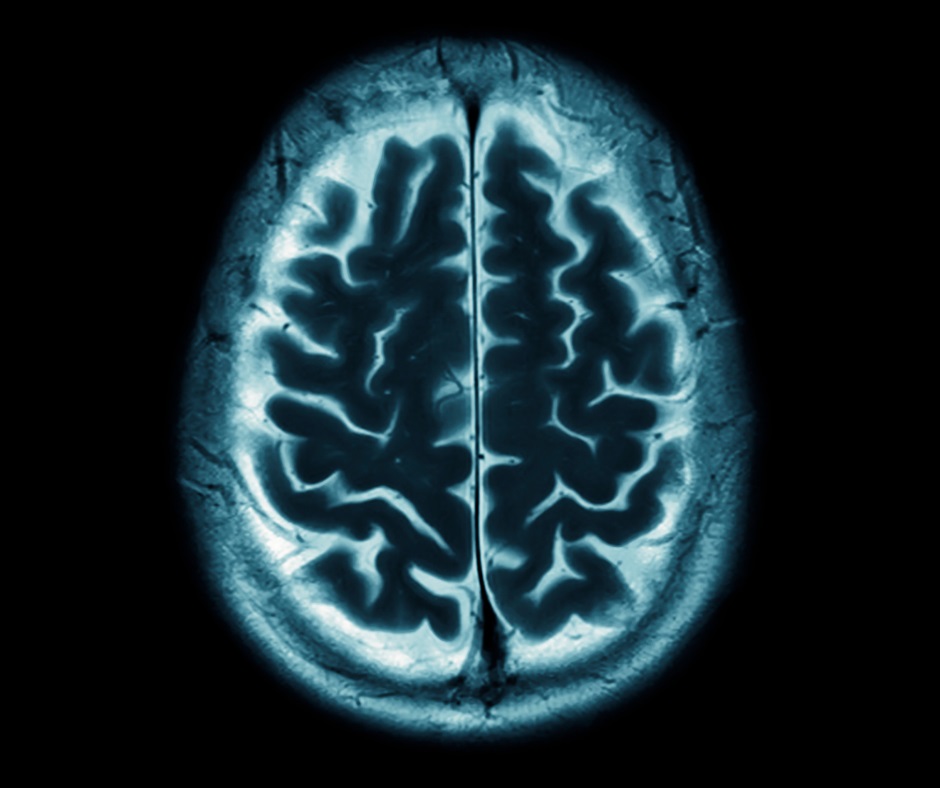

W czasie dorosłego życia każdego człowieka dochodzi do stopniowego, powolnego zmniejszania się objętości mózgu. Proces ten, nazywany atrofią mózgu, zachodzi znacznie szybciej u pacjentów ze stwardnieniem rozsianym (SM). Na szczęście, wczesne rozpoznanie choroby i włączenie wysoko skutecznego leczenia może hamować proces zanikania mózgu, co potwierdzają obserwacje z praktyki klinicznej lekarzy neurologów. Dzięki temu pacjenci pozostają sprawni, zarówno ruchowo, jak i mentalnie, mogą normalnie funkcjonować i wykonywać pracę zawodową.

Jeszcze do niedawna, w leczeniu stwardnienia rozsianego, koncentrowano się przede wszystkim na zmniejszaniu liczby rzutów tej choroby, redukcji ognisk zapalnych w ośrodkowym układzie nerwowym oraz zachowaniu sprawności fizycznej pacjentów. Obecnie parametrem coraz częściej branym pod uwagę przy ocenie postępu choroby oraz skuteczności leczenia jest także zanik mózgu. Przyspieszone tempo zaniku mózgu jest bowiem wykładnikiem zachodzącej neurodegeneracji, która prowadzi do ubytku funkcji neurologicznych, a co za tym idzie do utraty sprawności fizycznej oraz funkcji poznawczych. Pacjenci skarżą się na problemy z pamięcią, myśleniem i koncentracją, co utrudnia im codzienne funkcjonowanie i wykonywanie pracy zawodowej. Nasilony zanik mózgu sprzyja też przewlekłemu zmęczeniu oraz rozwojowi depresji i generalnie obniża jakość życia pacjentów ze stwardnieniem rozsianym. Kluczowe dla zahamowania procesu atrofii u chorych na SM – podobnie jak dla zapobiegania kolejnym rzutom choroby i postępowi niepełnosprawności fizycznej – jest szybkie rozpoznanie choroby i jak najszybsze rozpoczęcie skutecznego leczenia.

„Trzecia moja pacjentka ma także 33 lata i też zaczęła chorować ponad 10 lat temu czyli w 2012 roku. Po diagnozie zaczęła otrzymywać leczenie interferonem, ale już w pierwszym roku terapii choroba zaczęła się uaktywniać w postaci rzutów i zmian w mózgu widocznych w badaniu rezonansem magnetycznym. To spowodowało, że już w 2014 roku, czyli dwa lata po diagnozie można było włączyć leczenie lekiem drugoliniowym. Paradoksalnie, agresywny przebieg choroby okazał się być >>szczęściem w nieszczęściu<<, bo dzięki temu ta chora mogła szybko otrzymać leczenie wysoko skuteczne lekiem okrelizumab. Ta pacjentka pozostaje aktywna zawodowo i bez przeszkód pracuje. Co więcej, porównując obraz rezonansowy mózgów tych trzech pacjentek, bardzo wyraźnie widać, nawet bez wykonywania pomiarów wolumetrycznych, że im dłużej pacjentka była na leczeniu pierwszoliniowym, a krócej na drugoliniowym, tym objętość mózgu jest mniejsza. Oznacza to, że leczenie wysoko skuteczne hamuje proces zaniku mózgu” – podkreśla dr hab. Maciej Świat. Dla aktywnych zawodowo osób z SM, ważne jest, żeby stosowane leczenie było jak najmniej obciążające i nie wiązało się z koniecznością częstych absencji w pracy, co zapewnia terapia lekiem podawanym raz na pół roku.